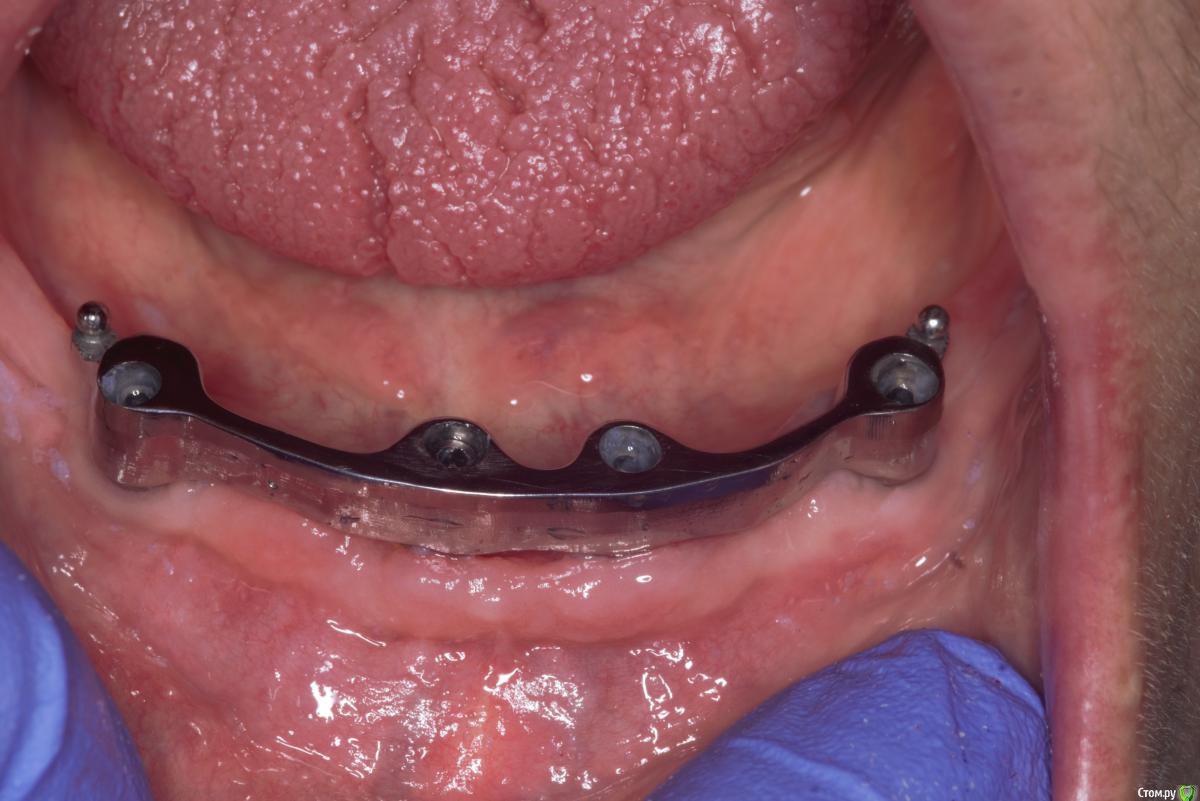

Прикручиваем балку post-36568-0-83457700-1566455323_thumb.jpg

Ответная часть в протезе post-36568-0-74785100-1566455400_thumb.jpg

Во рту post-36568-0-13353100-1566455461_thumb.jpg post-36568-0-30978400-1566455479_thumb.jpg

Панорама post-36568-0-16435400-1566455538_thumb.jpg как будто дистально балка прилегает хуже, но все держится без втулок. Пока что делать ничего не буду, понаблюдаем.